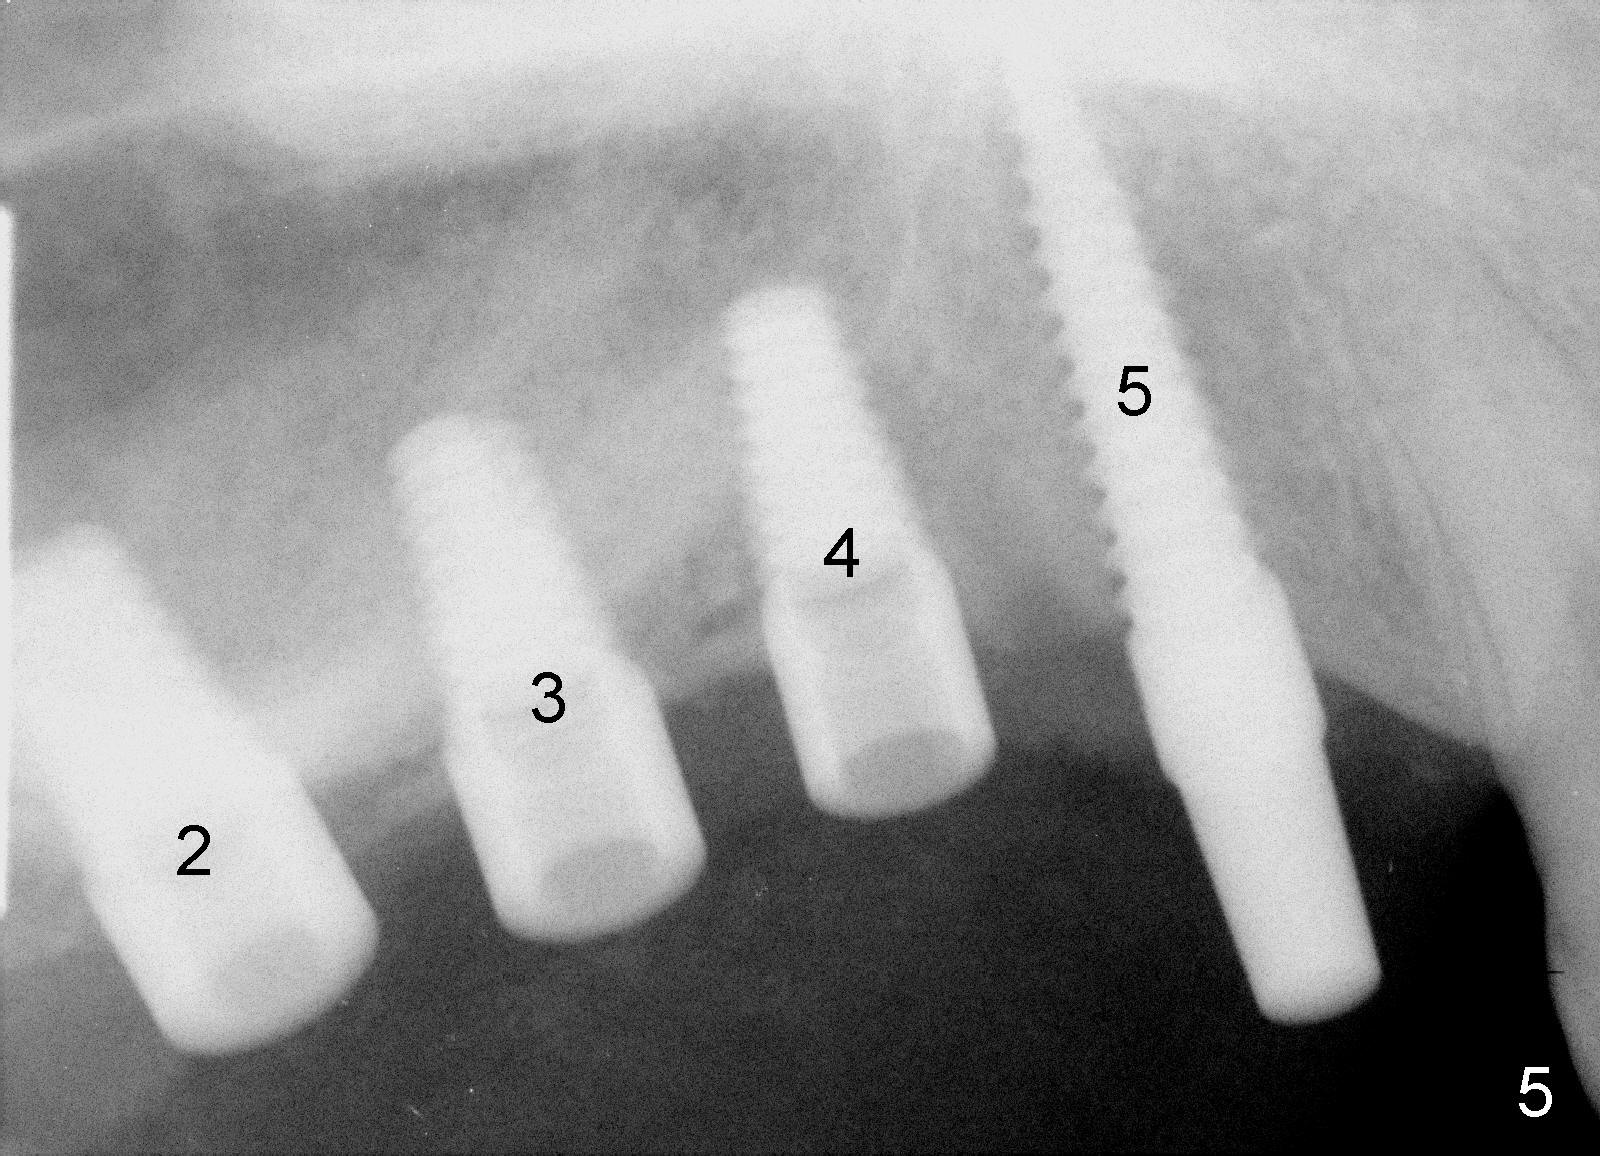

Fig.4 shows 4 implants in place with implant apex sticking into the sinus (>, which will be covered by bone graft). Fig.5 is a PA taken post bone graft, while Fig.6 is a section of panoramic X-ray showing the boundary of bone graft (arrowheads) after cementation of a provisional bridge. The latter satisfies the patient's request for cosmetics.